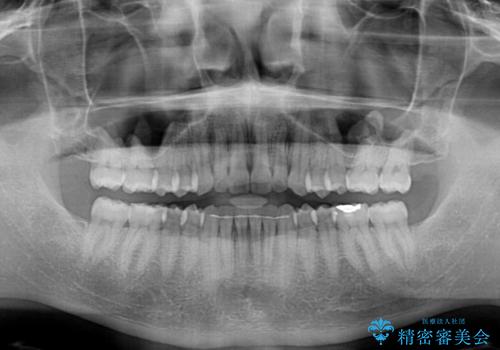

前歯のデコボコとクロスバイト インビザライン矯正治療

- 前歯のデコボコとクロスバイトを治したいとのことで来院された患者様です。

上下顎ともに歯列全体の側方拡大を行い、下顎前歯はIPR(歯と歯の間を削る)によってデコボコとクロスバイトが解消するように設計し、インビザラインにより治療を行うこととしました。

2年弱で終了する予定でしたが、途中来院されなかった時期があり、その後舌側転位している前歯を動かせるところまで動かしたいとのことで4年ほど治療を継続されました。